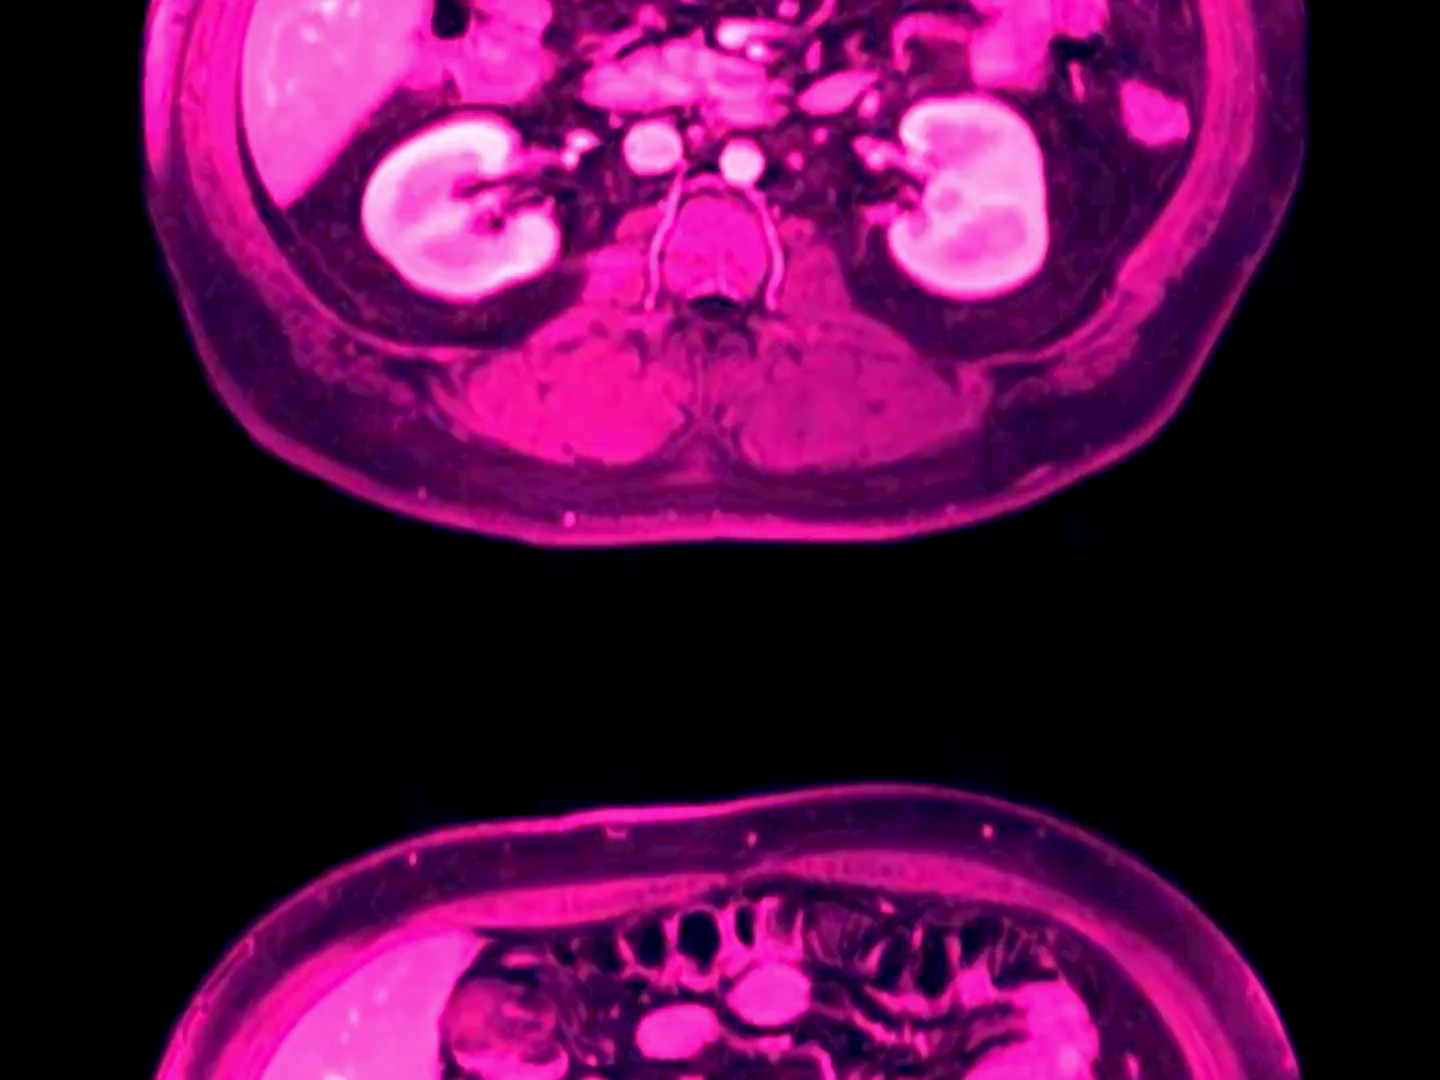

The film opens with some individual frames of film, scrolling vertically. We are looking at fluorescently colored x-ray images of a body part. The frames scroll faster and faster, blurring until they produce the characteristic illusion of movement which is the heart of cinema, morphing into colorful blobs, constantly changing shape. On the soundtrack, a low electronic pulsing gradually rises in pitch, demonstrating the aural equivalent to the persistence of vision illusion in film, as individual waveforms blur together to create a musical tone. In this way, oculorum signals its focus on the biological foundation of sensory experience.

This extended opening section features a montage of medical imaging: different computerized representations of cells, bones, and nerves, using technologies both new and vintage, and generally colorized in brilliant, saturated colors. Images which change on every frame overlap with sequences of smooth motion, presenting us with the illusion of motion while at the same time subverting it. A variety of film and video test patterns flash by, referencing the scientific and mathematical approach to understanding human vision.

We watch constantly transforming cell-like blobs which might be developing fetuses; they might represent cell mitosis. We might be inside the eyeball itself, that lens full of fluid and gel, flickering with electric signals. Orifices contract and expand, as long, sustained tones overlap. Organic sounds of string instruments and the human voice mingle with electronic tones. This colorful parade of representations of the body shows the brain’s obsession with images: we even try to understand our own experience of vision by creating images of it.